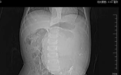

入院前查腹部 CT 平扫提示:腹腔内可见一巨大占位,截面约 92 * 132 mm,边界清,包膜完整,其内可见囊性、实性、钙化、线样分隔等多种成分。建议上级医院进一步就诊,为求进一步治疗遂至我院就诊。

入院专科查体:腹部膨隆,腹部偏左侧可触及一包块,大小触摸欠清,质中,活动差,与周边组织分界不清晰。

影像学检查:腹部 CT 平扫 + 增强如图,头颅、胸部 CT 未见明显异常。